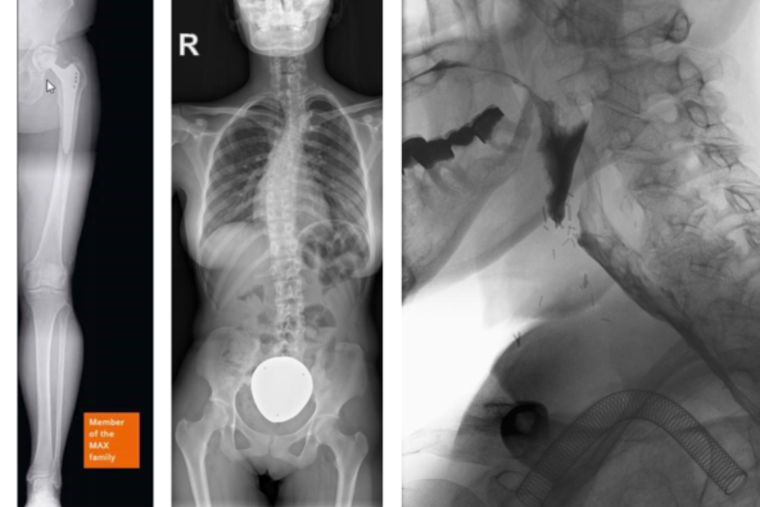

Radiologische Systeme müssen heute noch effizienter betrieben werden. Das Multitom Rax kombiniert mehrere Untersuchungsverfahren in einem System, so können beispielweise kleine interventionelle Eingriffe z.B. durchleuchtungsgesteuerte Punktionen der Gelenke zur Schmerztherapie durchgeführt werden. Auch die Darstellung der gesamten Beinachse zur optimalen OP-Vorbereitung bei Gelenksersatz oder der gesamten Wirbelsäule vor Korrekturoperationen von Fehlstellungen gehören zu den Aufgaben des neuen Multitom Rax Systems. Ferner ist es mit unserem neuen Gerät möglich einen sogenannten Breischluck anzufertigen, bei dem der Schluckakt sichtbar gemacht wird, um zum Beispiel Schluckbeschwerden oder die Refluxkrankheit zu diagnostizieren.

(Bilder: Siemens Healthineers)